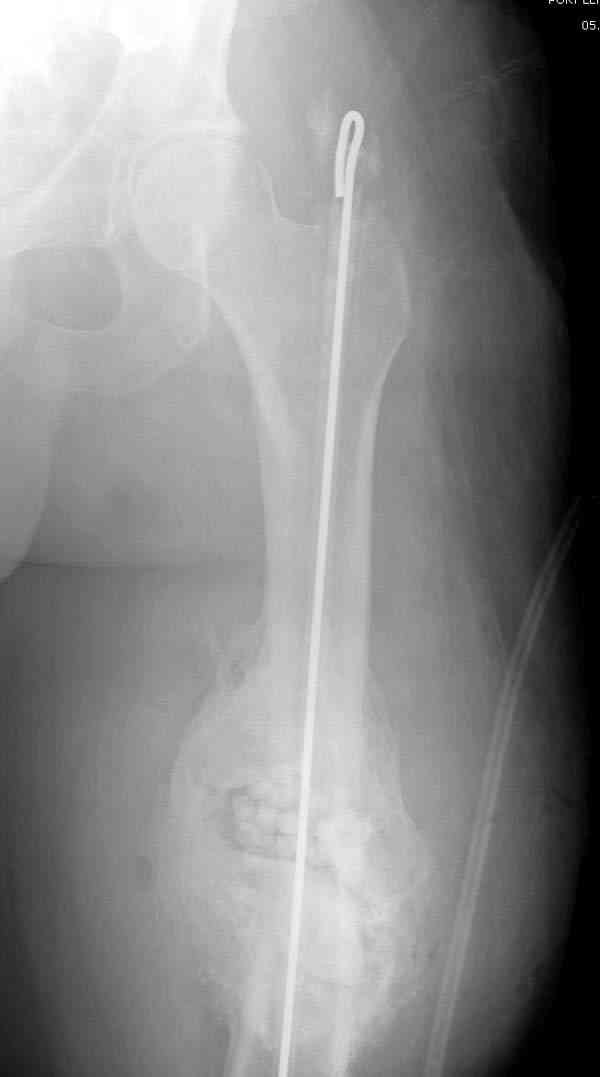

подготовка гвоздя

7-8 послеоперационные